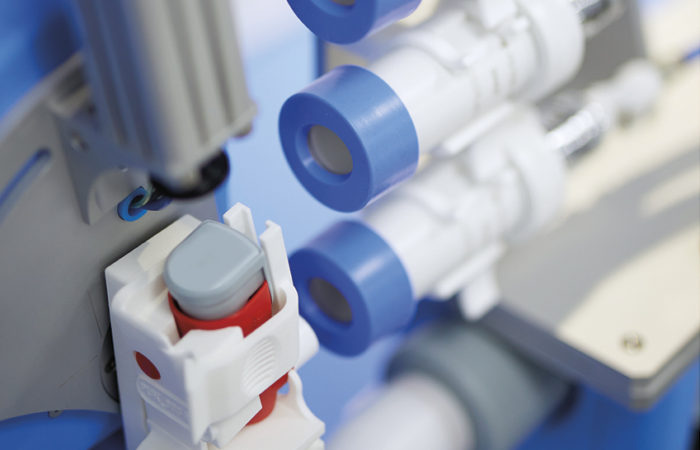

Figure 1: eFlow Integrated nebuliser platform.

Figure 2: Illuminated nebuliser and

vibrating controller.

The second element to guide patients’ breathing patterns is the user interface on the device. By providing intuitive instructions directly via an illuminated mouthpiece assembly and a vibrating controller, PARI’s new eFlow integrated nebuliser platform effectively trains the patient on the correct breathing pattern during inhalation. A pressure sensor collects real-time data from the inspiratory flow, translating this information into haptic and visual signals that inform the user on whether or not the inhalation is optimal (Figure 2).